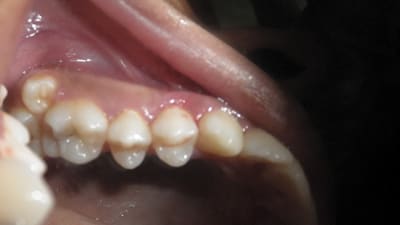

Case Reports Periodontics Implantology Clinical Management of Type 3 Recession Defects With Immediate Implant and Provisional Restoration Therapy: A Case Report By Dennis Tarnow, DDS, Stephen J. Chu, DMD July 01, 2017 8 min read